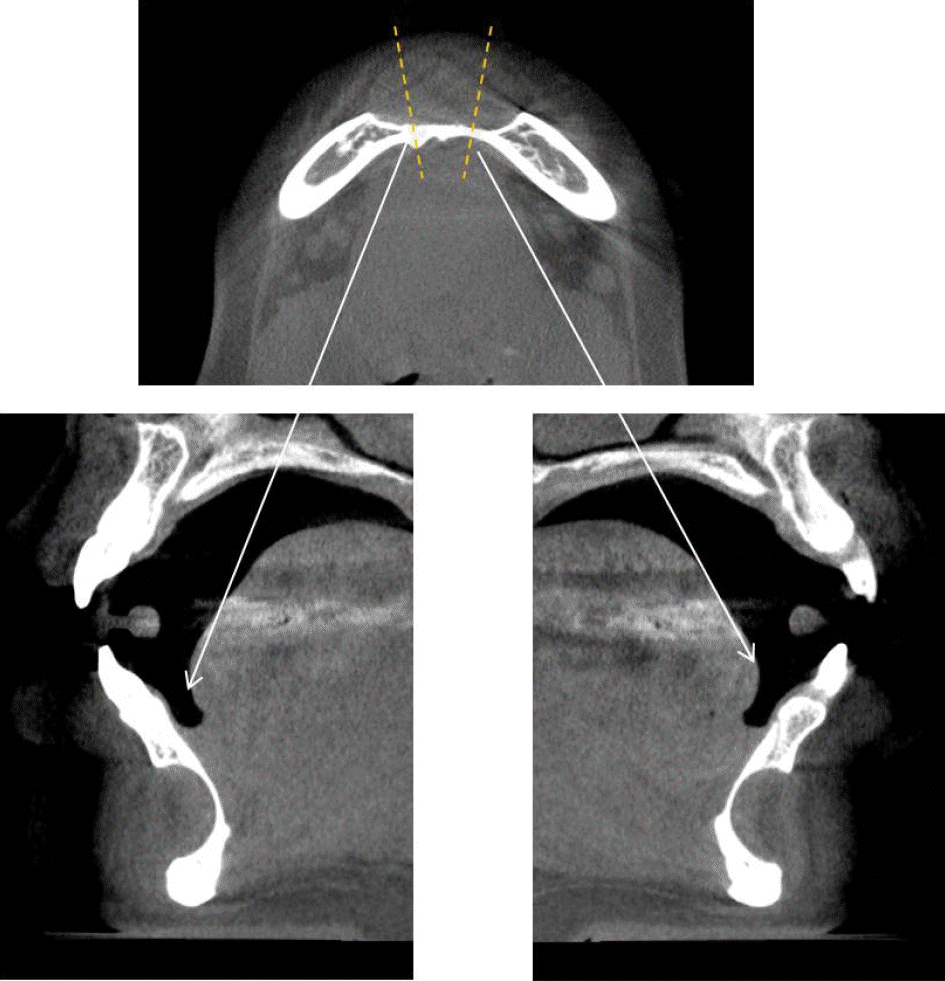

Figure 2.

Cone-beam computed tomographic 3-dimensional reconstruction image. A peripheral bone defect is observed extending from the labial to the lingual aspect of the mandible, rather than a centrally located intraosseous lesion.

Figure 4.

Cone-beam computed tomographic cross-sectional view of the mandible clearly demonstrates a peripheral bone depression extending from the labial to the lingual cortical plate.

32세 여성 환자의 파노라마방사선영상에서 하악 전치부 낭이 관찰되어, 정확한 진단을 위하여 본원에 의뢰되었다. 특별한 임상증상은 없었다. 파노라마방사선영상에서 하악 우측 제1소구치에서 좌측 제1소구치 치근하방에 경계가 명확하고 피질골성 변연을 가진 타원형의 방사선투과상이 관찰되었다(Fig. 1). 방사선투과상은 해당치아들과는 무관하여 치근단낭이 배제되었고, 단순골낭의 가능성을 염두에 두고 콘빔CT 검사를 시행하였다. 콘빔CT에서 중심성 골내 병소가 아닌 악골의 순측에서 설측으로 함몰된 변연성 병소가 관찰되었다(Fig. 2). 병소의 경계는 매우 평활하였고, 단면상에서는 넓은 접시모양처럼(Fig. 3), 악골 절단면상에서는 반달모양처럼 함몰되어 있었다(Fig. 4). 설측 피질골은 비박되어 있었으나 천공은 관찰되지 않았다. 함몰된 부위는 공기가 아닌 연조직의 방사선투과상으로 채워졌으나, 콘빔CT에서는 대조도가 낮아서 연조직간의 감별이 가능하지 않았다(Fig. 5). 관찰된 턱 끝 부위의 골 함몰이 해부학적 변이인지 아닌지를 감별하기 위하여 환자의 과거 병력을 알아보았다. 환자는 2년 전에 턱 끝 부위에 미용 필러 시술을 받았다고 하였다. 방사선영상소견과 문진결과를 토대로, 미용 필러와 관련된 골흡수를 의심하였다. 이후 외과적으로 미용 필러 제거와 함몰된 부위에 골이식이 시행되었다. 수술 중에 육안으로 남아있는 미용 필러와 작은 석회화 물질들이 확인되었다. 수술 후 생검에서 다핵거대세포와 결절석회화가 관찰되었고, 피부석회화(calcinosis cutis)가 의심된다는 결과를 받았다. 이상의 술 전 검사 및 술 후 소견을 종합하여, 파노라마방사선영상에서 관찰된 방사선투과상은 치성낭이나 해부학적 변이가 아니고 미용 필러에 의한 하악골 순측 골흡수로 최종 진단되었다.